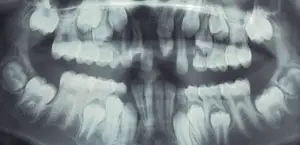

SURGICAL EXTRACTION OF IMPACTED PRIMARY MOLAR

A 8 year old boy reported to the department with a complaint of missing teeth in the lower left back teeth region. While recording the history his mother reported that the tooth in that region had not erupted. On clinical examination an edentulous space was seen and the first permanent molar had inclined towards this edentulous space. An OPG and IOPA were taken that showed the presence of an impacted primary second molar. Underlying it was a developing permanent 2nd molar. A surgery was performed for the removal of this impacted tooth which was followed by placement of a space regainer to distalize the permanent 1st molar.